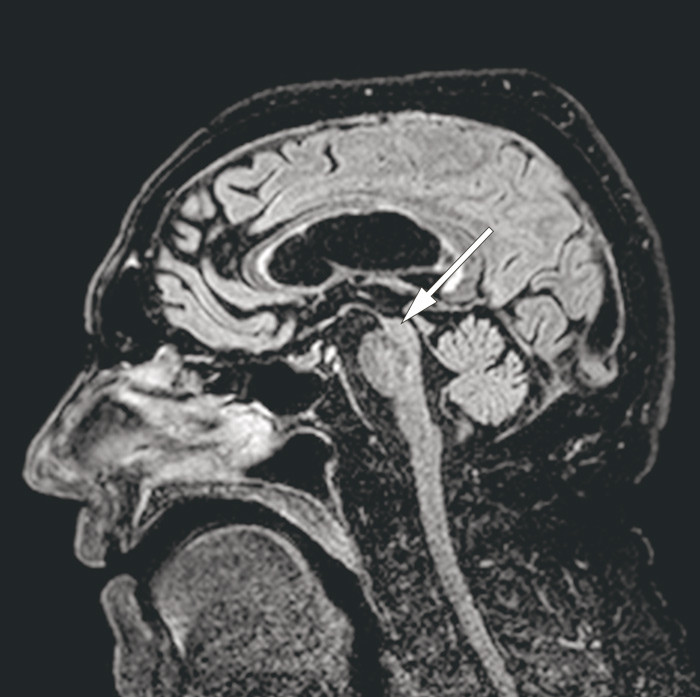

MR-undersøkelse av hjernen viste en uttalt atrofi av mesencephalon som i sagittalsnitt får hjernestammen til å ligne en fugl i profil, gjerne omtalt som kolibritegn eller pingvintegn (pil). Dette er et typisk bildefunn ved den sjeldne nevrodegenerative tilstanden progredierende supranukleær parese (1).